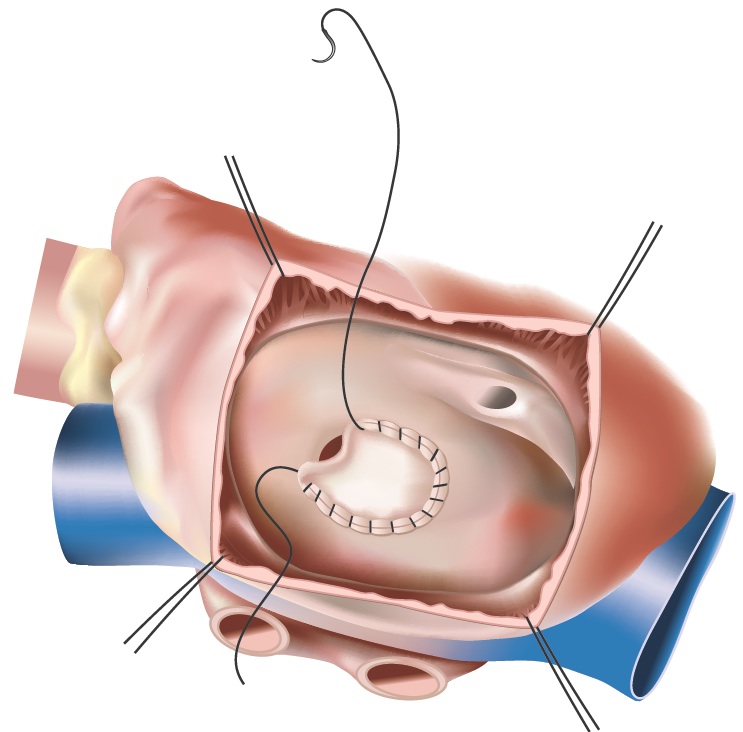

Smaller ASDs can simply be closed using a suture and oversewing the hole. For larger ASDs, a patch is usually used to close the hole. This patch can be taken from the pericardium (the sac that surrounds the heart) or from synthetic materials such as Dacron or Teflon.

Figure 2 - Closed ASD